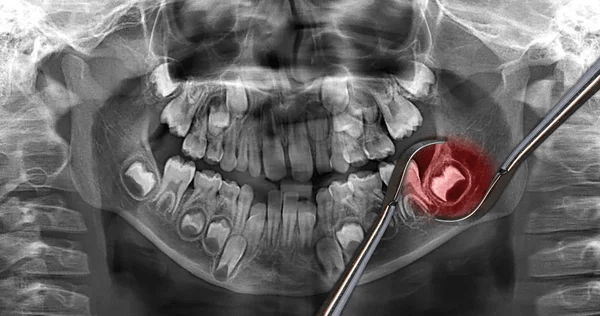

But nosy old WordPress insists I tell all about personal experience as usual. In fact for me all of this work has been dental (as in the blog linked here which tells the story of one of those experiences).

There was however more to come in that same story. The pain I felt from that incision continued and developed for a further three months, during which my own dental surgeon’s indicated rather consistently that my pain was psychosomatic – would after one try prescribe no antibiotics or strong painkillers, and I lived on Paracetamol and Ibuprofen in series – then not dealing with the pain which extended from my throat, to nose, ear and to severe headaches. Eventually my local dentist referred me back to their private surgeon, again at Brampton, and this time my husband took me because I feared driving with the pain.

The dentist operated again removing another tooth adjacent to the site of the wisdom tooth and then scraping out decay left in the old wound of the wisdom tooth which had caused the original pain. The sensation of scraping and cutting could not at the time be felt as pain – being heavily anesthetised locally but later it was horrendous for at least three days. After three months of pain, you trust the skill of no-one’s hands and I had to get better to trust again. And of hands – skilled or otherwise – I remember very little – just the look and feel of cutting, gouging and scraping tools.